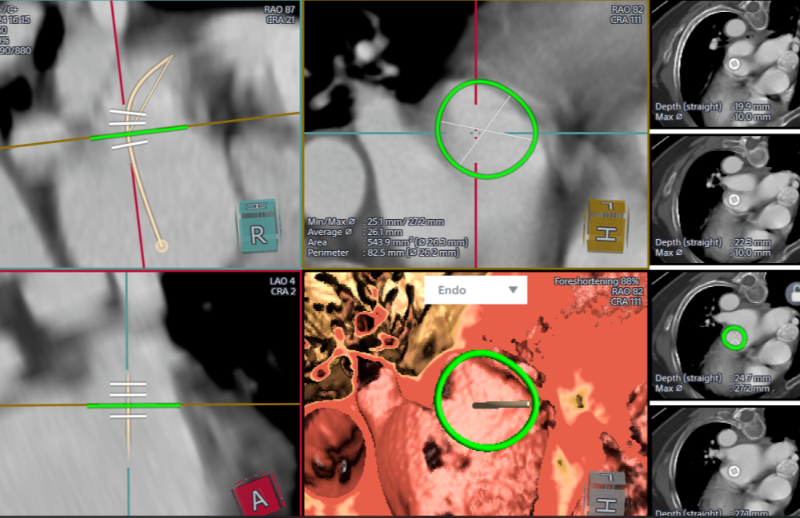

經過完善的術前CT和全面的Truplan軟件術前分析準備。在介入室的全面配合下完成該患者的術前準備工作,謝桂庭進行房間隔穿刺,精準定位穿刺位點。行左心耳造影,造影結果顯示開口28mm左右,深度32mm左右。結合術前Truplan結果以及術中DSA測量結果,選用WATCHMAN 33mm封堵器進行封堵。